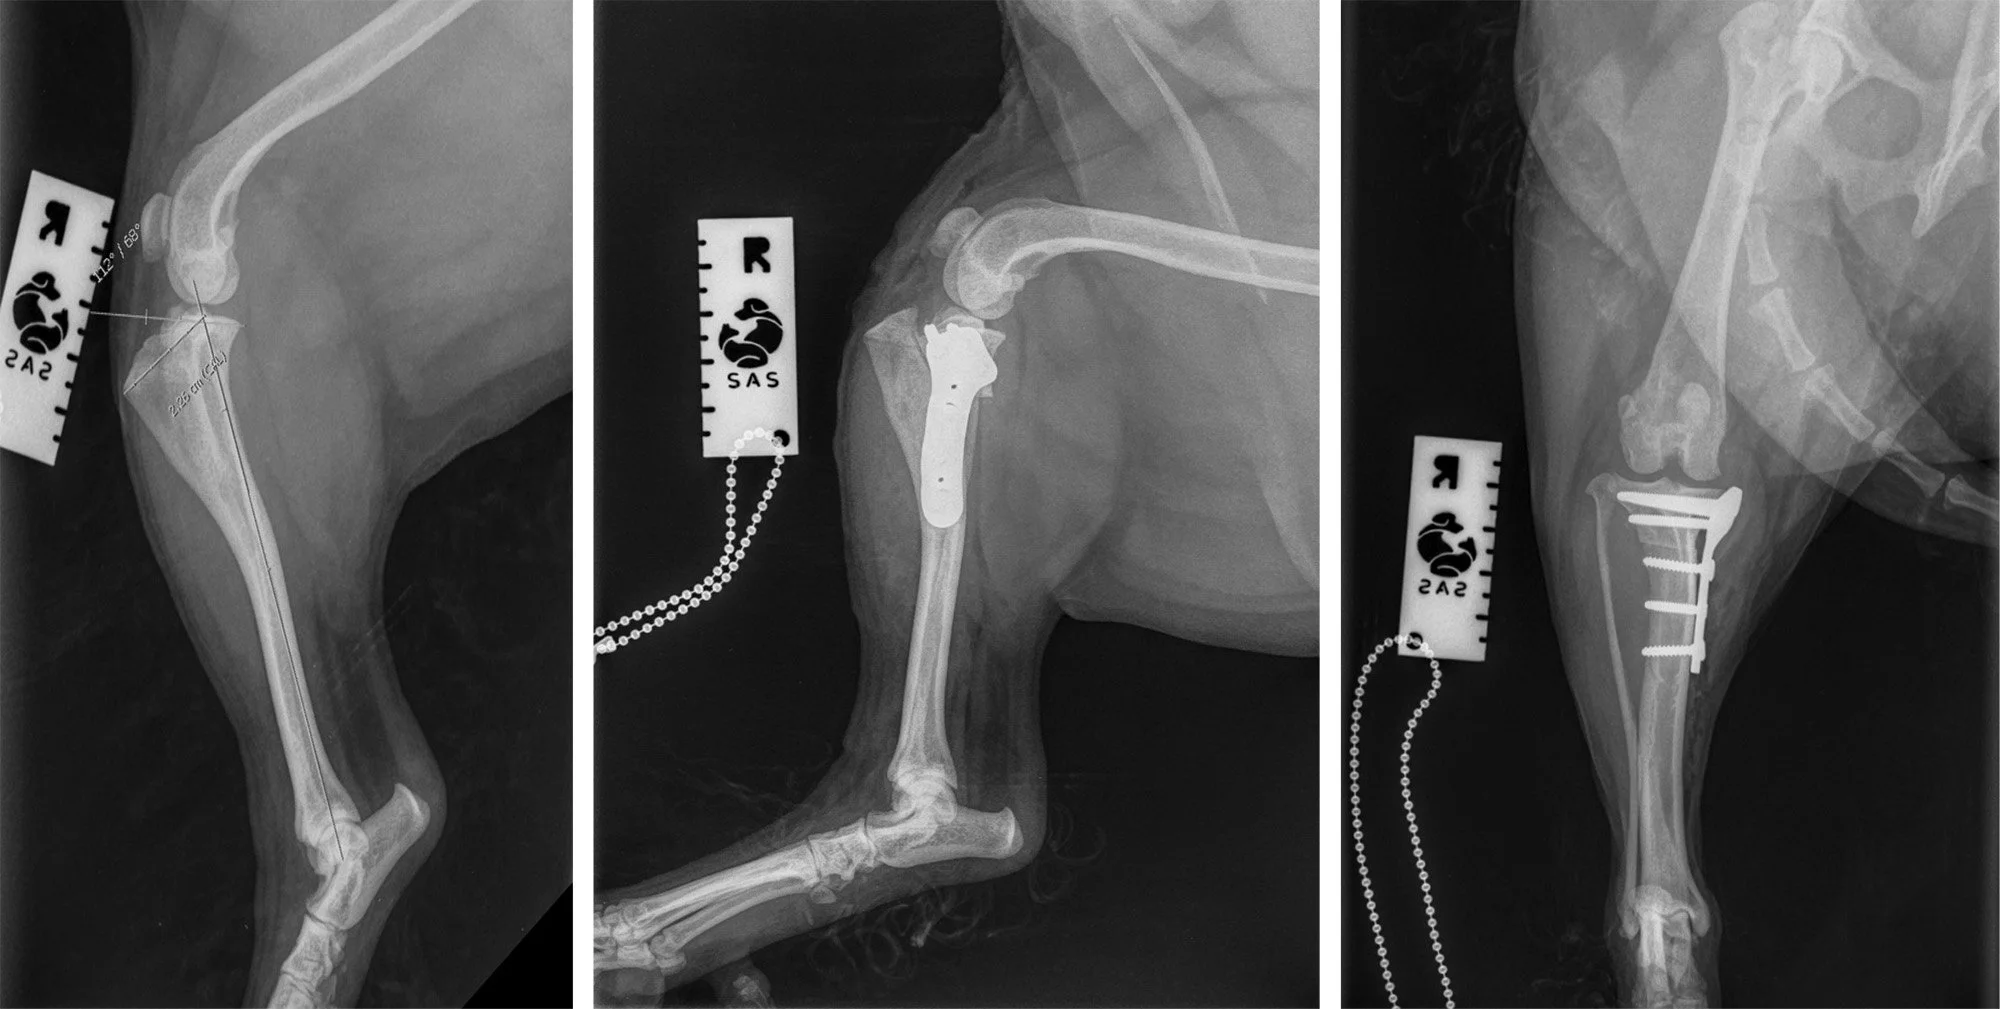

X-ray images of a dog's leg with surgical screws, plates, and a chain for measurement, showing different angles of the leg.

In-House Referral Services

We offer our clients the convenience of expert visiting surgeons right here at our clinic in Cobham, Surrey. This service allows your pet to receive expert-level care in a familiar environment, helping reduce anxiety and promote better recovery.

• Orthopaedic Surgery